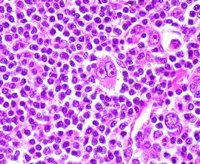

El Grupo Oncológico para el Tratamiento y Estudio de Linfomas (GOTEL) denuncia que cada vez hay menos oncólogos que se dediquen a esta patología, lo que hace que sólo un 6 por ciento de los pacientes sean vistos por profesionales especializados en sus primeras fases de diagnóstico y que se retrase el inicio del tratamiento.

De los dos grandes grupos de linfomas, el no Hodgkin representa el 85 por ciento del total y cada año se diagnostican en España más de 6.100 nuevos casos. La incidencia se encuentra en la franja media/alta respecto a Europa y el resto del mundo, aunque se ha incrementado en los últimos años.